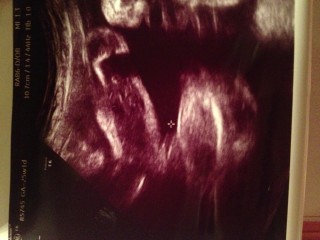

胎児スクリーニング検査で初めて4Dエコーで診てもらいました! 776gで25w0d相当。やや大きめ。 右目を隠してるのは胎盤だそうです☆ 前回から言われていた性別も男の子でほぼ確定です。 心臓をチェックしてる時の元気な拍動を見て、感動で泣きそうになりました!!